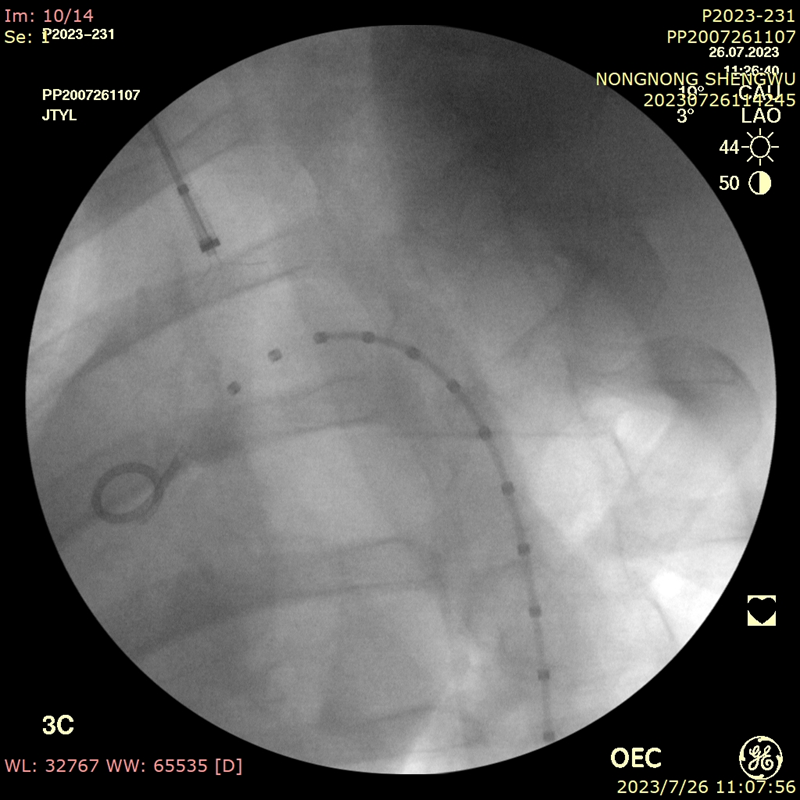

后释放支架预开窗病例

导丝破膜,各角度反复确认